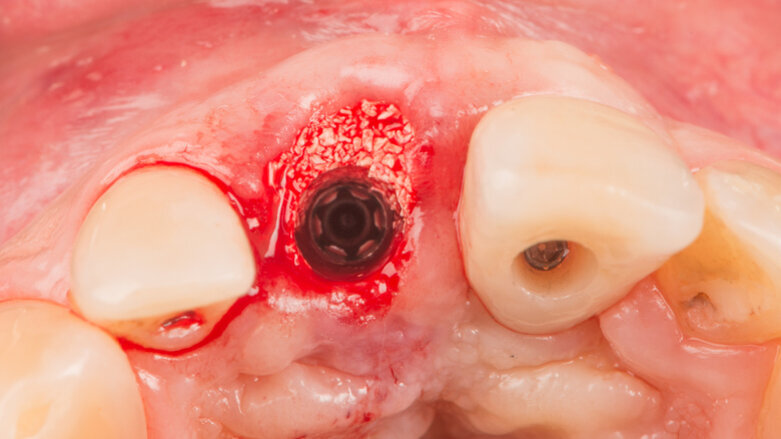

Extraction and socket preservation of tooth #12

Three months after placement, tooth #12 was extracted (Fig. 15), and a socket preservation procedure was performed. The socket was filled with cerabone (Fig. 16) and closed with a free gingival graft taken from the maxillary tuberosity (Fig. 17). A cantilevered temporary bridge was then torqued to 35 N cm.